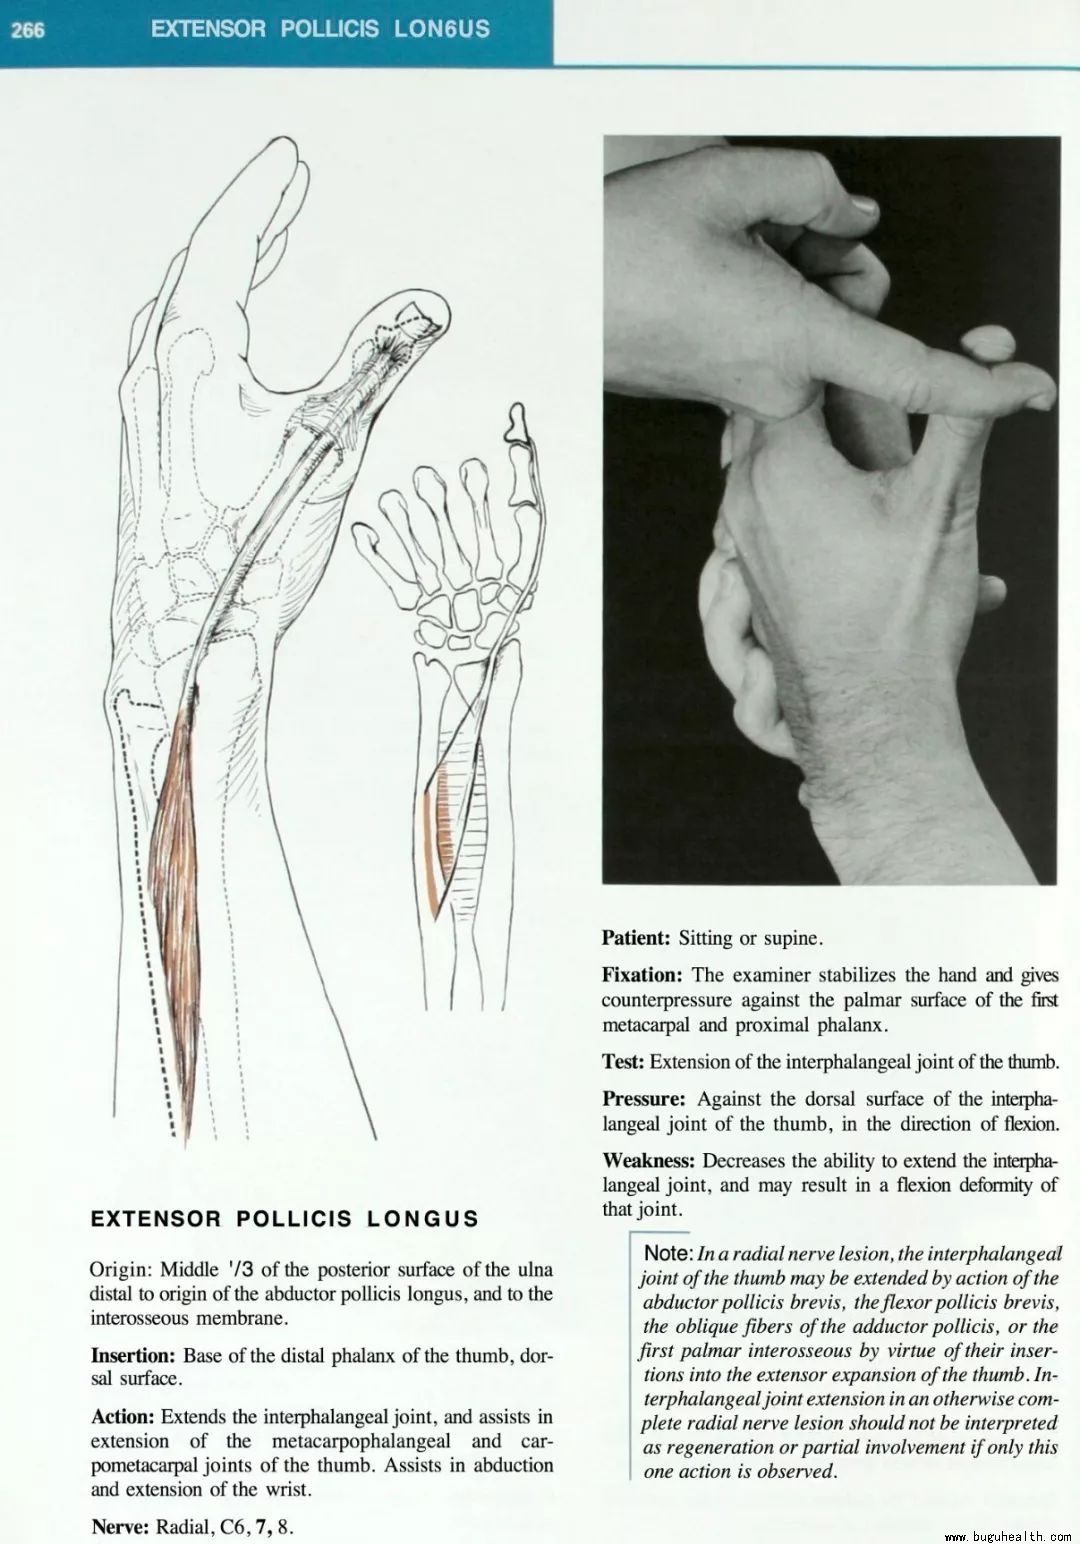

- 布骨医学科普:肌肉测试与功能,PT的基本功! 布骨康复医疗中心 ,2022-03-17

- 手动肌肉测试(Manual muscle testing)在肌骨康复中用于评估肌肉和肌腱生成力量的能力。在康复领域中,肌肉测试是评估肌肉是否存在损伤和缺陷的重要工具,包括肌肉力量,肌肉耐力和肌肉爆发力等。肌肉功能损伤(Impairment)可能是来自于一系列问题,例如肌骨损伤,心血管功能受损,肺功能.....